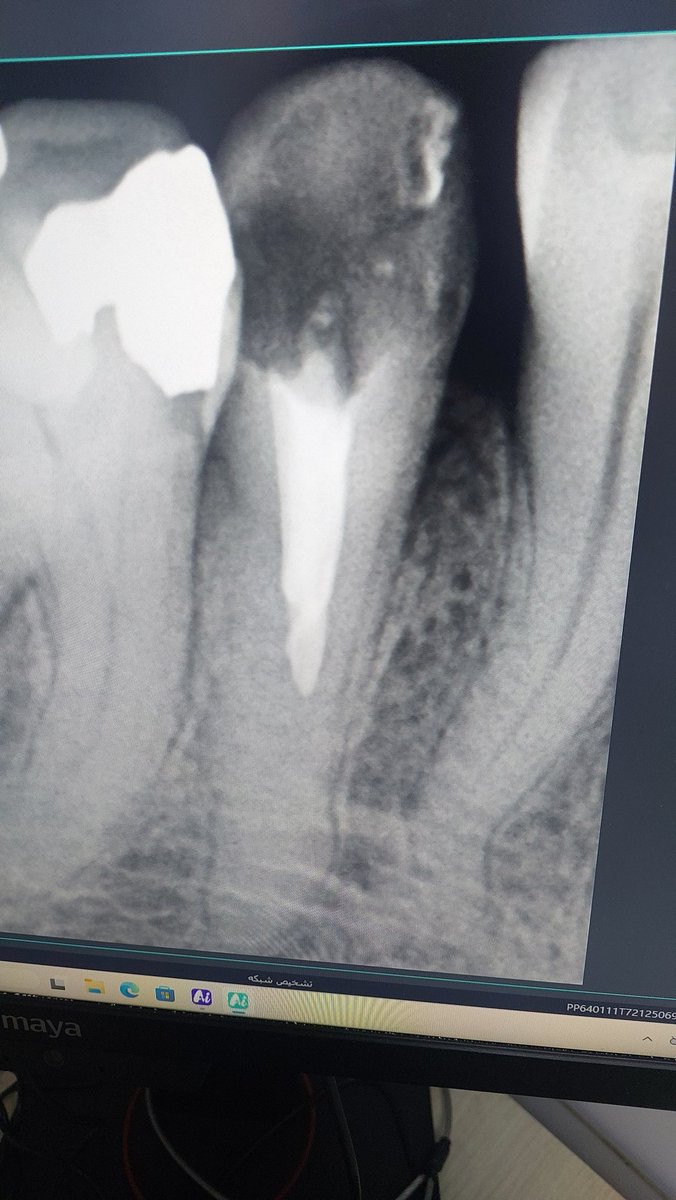

@shiretaziyee بخدا من که خودم دندونپزشکم تعرفه اندو مولر(دندون سخت) با ترمیمش ۶۱۰۰ عه، تازه کلینیک نهایتا ۴۰ درصدش رو به من بده!

تعرفه ها رو بردم بالا اندو ۶ = ۸ تا ۹ تومن دندون ۷ = ۸.۵ تا ۹.۵ روکش ۸ تا ۹.۵ ( امروز تصمیم گرفتم فک کنم خیلیه ولی خیلی بابتش وقت میذارم) پست بیماری که خودم اندو نکرده باشه ۵ تومن دندون ترمیم یک تا پنج : ۷ تا ۷.۵ ترمیم همون ۳.۵ تا ۴ کشیدن هم از ۸۰۰ شورع میشه